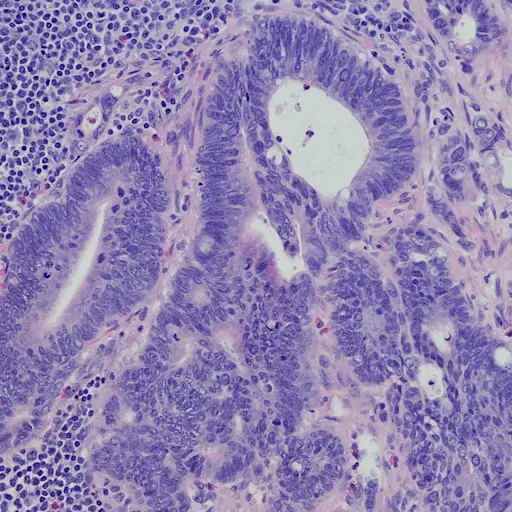

再一次,可能是的。但比勒博士说,为了知道哪种药物对你有效,病理学家对肿瘤进行基因测试以检查某些突变是很重要的。这是所有4期患者都应该做的事情,不管你的肿瘤最终是否有与已经使用的治疗方法相同的突变。她说:“也可能有临床试验选择和药物用于治疗具有这种突变的不同类型的癌症。”